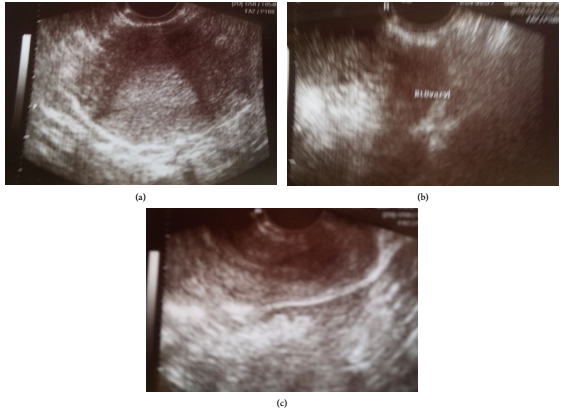

每隔2天进行一次β-绒毛膜促性腺激素水平的定量检查,结果显示胎儿发育不稳定(第一次检测4113mIU/ml,第二次检测3904mIU/ml,第三次检测4207mIU/ml),可能是异位妊娠的迹象。入院时的实验室值为Ht 33.9%,Hb 10.8% gr/dl、PLT 243x10^3/ml、WBC 9.9x10^3/ml、NEUT占79.9%,凝血机制及生化检查未见病理改变。妇科双合诊检查显示,子宫颈和右附件触诊时严重敏感。经阴道超声(图1a-c)显示子宫内膜腔内无妊娠囊,右附件解剖区域有不确定的肿块,道格拉斯囊内有血凝块。

图1. 经阴道超声图像,支持异位妊娠的诊断。(a)子宫内膜腔中未见妊娠囊;(b)右侧附件解剖区肿块;(c) 道格拉斯囊内有血凝块